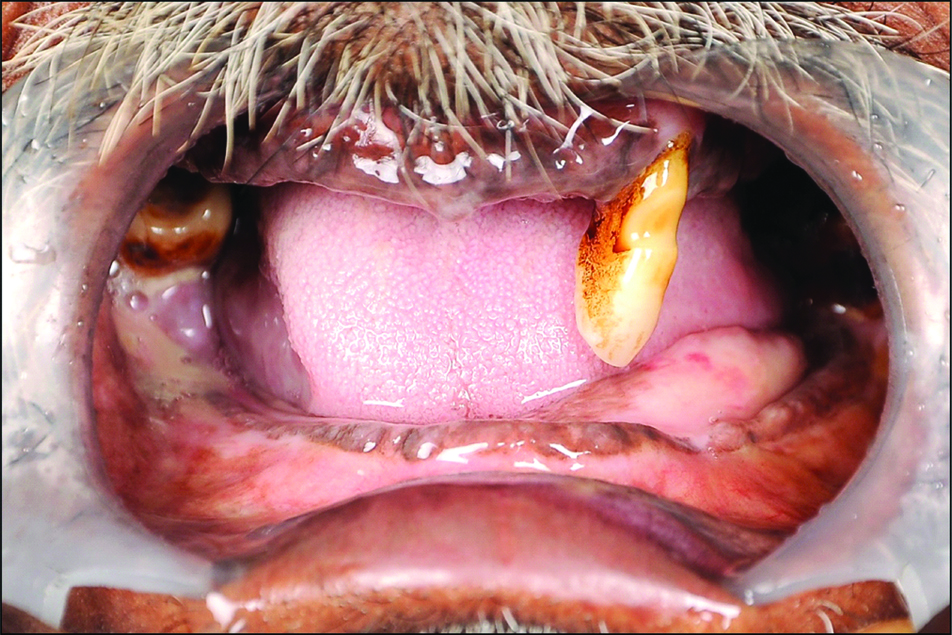

No extra oral bruise, laceration or bleeding was present. Intraoral examination revealed the mandibular ridge to be atrophic and partially edentulous maxillary and mandibular arches, with maxillary left canine (#23) being supra erupted and mandibular arch’s isolated teeth mandibular left third molar (#38) and mandibular right third molar (#48) presented with Grade II mobility [Table/Fig-1].

Preoperative intraoral view.